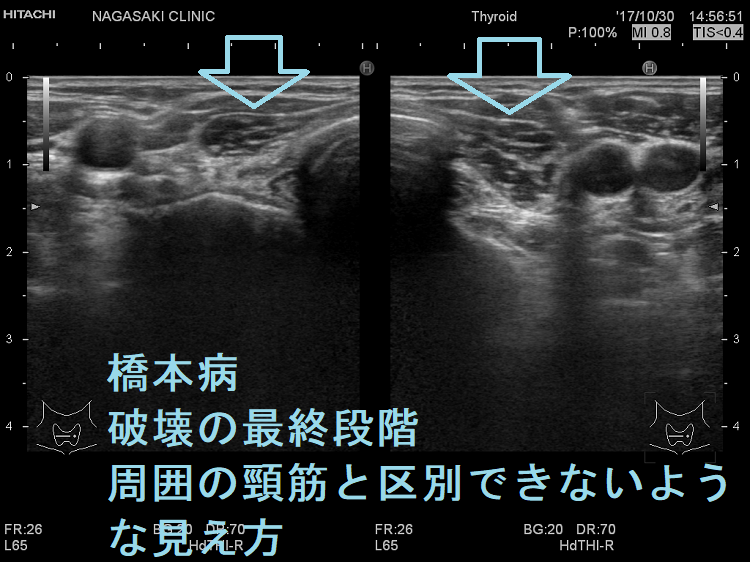

橋本病の破壊抗体[抗サイログロブリン抗体(TgAb)、抗甲状腺ペルオキシダーゼ抗体(TPOAb)]が合併しなければ、超音波(エコー)画像での甲状腺内部は正常そのもの、サイズだけが萎縮。

橋本病(慢性甲状腺炎)を合併すると、甲状腺の萎縮が明らかでない場合がああります。

重度の甲状腺機能低下症なのに、甲状腺超音波(エコー)検査で破壊の程度が軽ければ、萎縮性甲状腺炎を疑います。